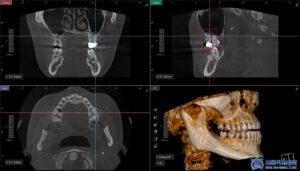

CT상에서도 뿌리 끝 부위에

염증 병소가 보다

명확하게 확인되었습니다.

파노라마에서는 평면적으로 보였다면,

CT 촬영을 통해 염증의 위치와 범위,

주변 뼈 손상 정도까지

입체적으로 확인할 수 있었고,

그 결과 해당 치아는 신경치료가

필요한 상태임을 판단할 수 있었습니다.